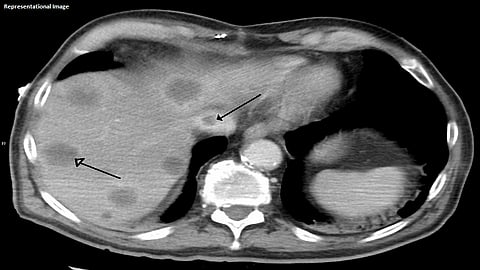

'बड छिआरी सिन्ड्रोम' आजारात यकृताकडून हृदयाला रक्तपुरवठा करणाऱ्या नसा अतिशय बारीक होत जातात. त्यामुळे रक्तपुरवठ्याच्या कार्यात अडथळा निर्माण होतो. परिणामी रुग्णाचे पोट फुगते, शरीराच्या काही भागांवर सूज येते. या आजारामुळे माझ्या शरीरातील शुद्ध रक्त हृदयापर्यंत जात नसून, यकृताचे कार्यही त्यामुळे बिघडले आहे. या आजारामध्ये यकृत प्रत्यारोपण हा शेवटचा पर्याय असल्याचे यकृतप्रत्यारोपण तज्ज्ञ डॉक्टरांचे स्पष्ट मत आहे.